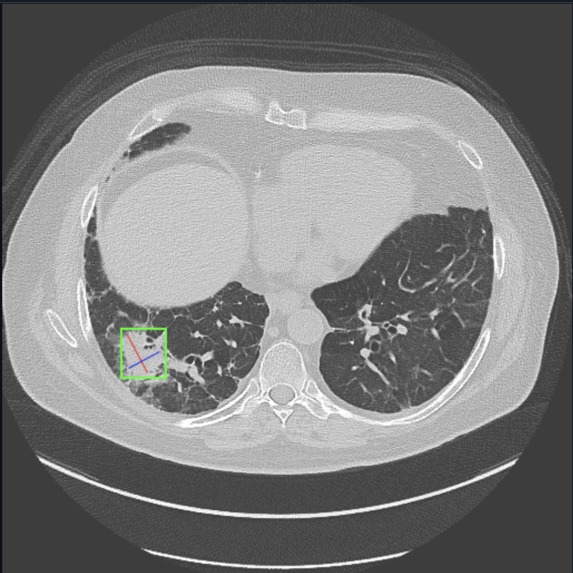

Our project uses AI to analyze X-ray scans/datasets to detect and predict lung cancer.

The project was built using the NVIDIA AI Workbench and various AI/ML libraries such as Torch and Scikit-learn. We used an extensive lung cancer dataset from Kaggle (https://www.kaggle.com/code/guslovesmath/lung-cancer-ml-classification/input) to train the Random Forest model, as well as X-ray scans of healthy lungs and those with cancerous growths to train our deep learning model.

Throughout this project, we learned the intricacies of medical image analysis, particularly when dealing with x-ray scans. We gained a deeper understanding of how to preprocess image data, handle large datasets, and apply machine learning techniques such as convolutional neural networks (CNNs) for image classification. Additionally, we became more familiar with medical imaging datasets and the ethical concerns of using sensitive health data in AI applications. Moreover, we learned the importance of teamwork. By putting our heads together, we were able to boost progress and receive instant feedback for our ideas from one another. Debugging became easier as well as three heads were more likely to spot the error than one person would. Work also turned out to be more fun as we would spend countless hours working together while socializing.